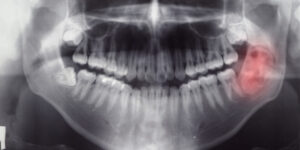

أورام وتكيُّسات الفك هي أورام أو آفات نادرة نسبيًّا تظهر في عظم الفك أو الأنسجة الرخوة في الفم والوجه. قد تختلف أورام وتكيُّسات الفك -التي